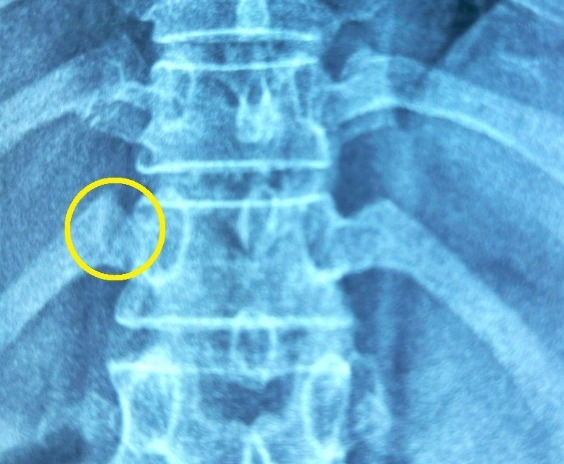

Kết quả phim chụp X-quang cho thấy xương sườn số 12 bị gãy phạm khớp sườn cột sống. Bác sĩ xử trí laser giảm đau, thuốc giảm đau tại chỗ. Sau 15 phút, bệnh nhân có thể ngồi dậy, sau đó dần tỉnh táo và đi lại.